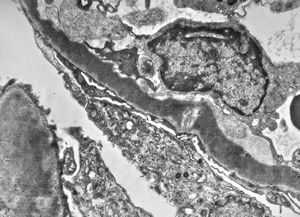

F,14y. | Alport syndrome - split and laminated, thick/thin basement membranes